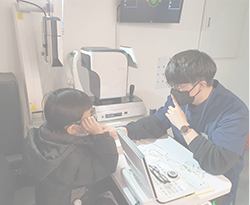

혁신적 검안 시스템

일반적으로 눈을 안경에 맞추는 것이 아닌, 임상 데이터를 기반으로 안경을 눈에 알맞게 맞추는 고도화된 검안 과정 도입

전문 검안사 교육&양성

검증된 검안 프로세스 교육을 통해 전문가 과정을 수료하고 임상 경험과 최신 정보를 보유한 ICU만의 검안사 양성